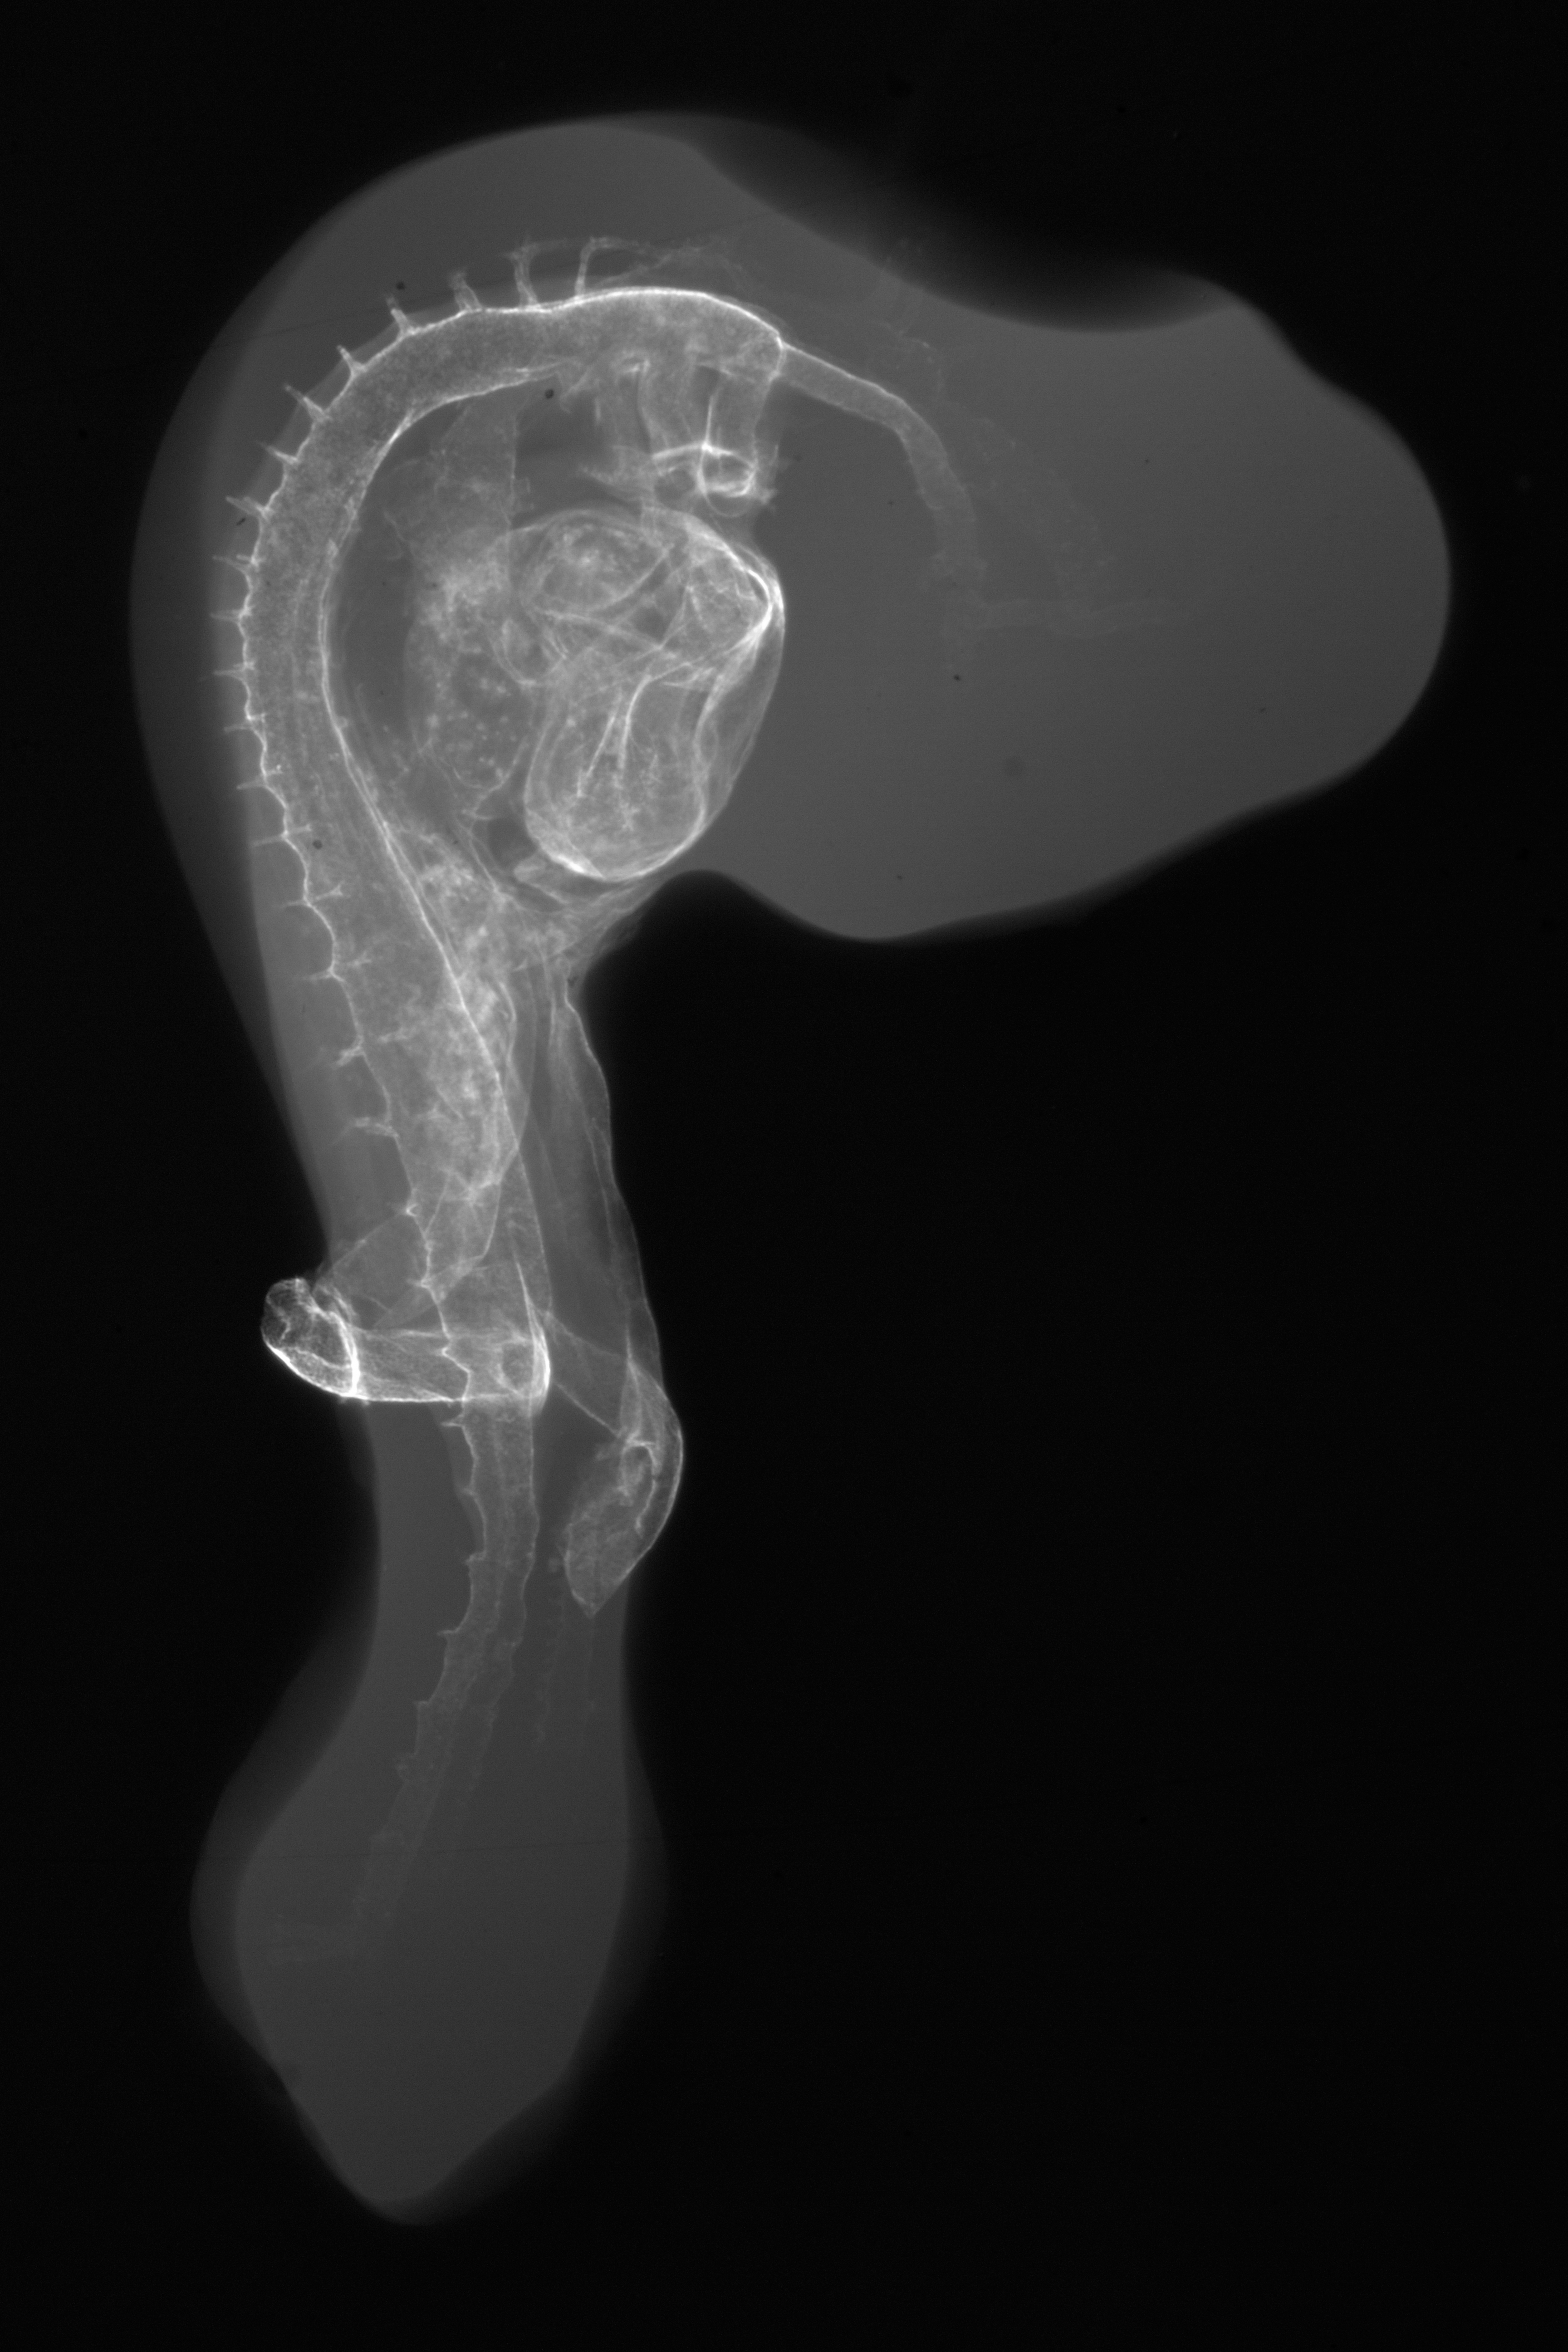

Chick Embryo Microangiography

Hamburger-Hamilton (HH) Stage 18 (approx. 3 days)

X-Ray Micrographs